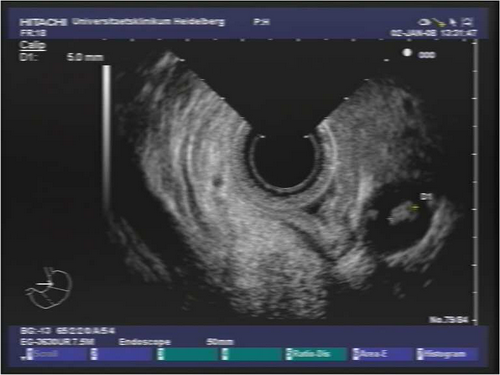

Endosonografie: In der durchgeführten Endosonographie zeigte sich ein ulzerierter Magentumor im Bereich des Korpus-/Antrumübergangs. Endosonographisch wird die Muskularis infiltriert, an einigen Stellen auch die Serosa, benachbarte Strukturen sind nicht infiltriert, somit uT3 (max. Dicke 9 mm). Es finden sich lokoregionär auch im Bereich des Tr. coeliacus mehrere LK bis 10 mm. Beim Rückzug stellten sich zudem paraösophageal mehrere deutlich vergrösserte, echoarme und polyzyklisch begrenzte, suspekte LK dar.